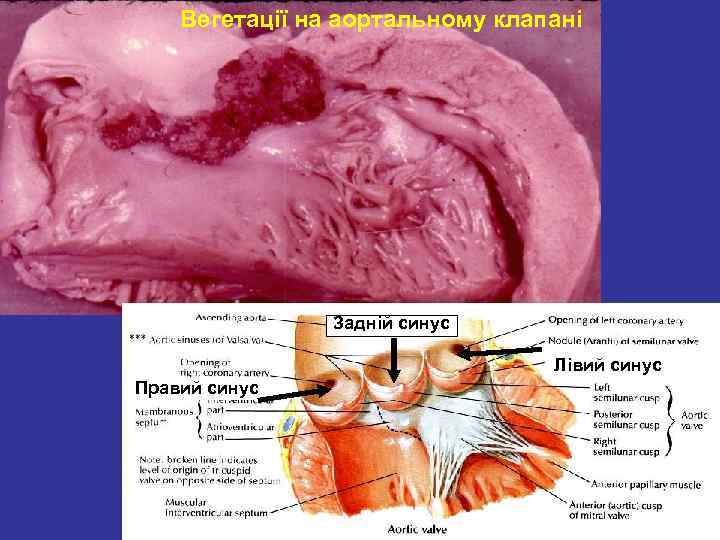

Вегетації на аортальному клапані Задній синус Лівий синус Правий синус

Основні патоморфологічні прояви ІЕ при уражені АК Вегетації 767 (86, 6%) Перфорації 109 (12, 3%) Абсцеси 279 (31, 5%)

Основні патоморфологічні прояви ІЕ при уражені АК Вегетації 237 (67, 5%) Перфорації 227 (62, 4%) Абсцеси 32 (8, 0%)